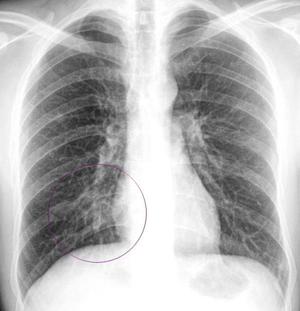

Очаговая пневмония на рентгене

Очаговая форма болезни проявляется легким лейкоцитозом, незначительными хрипами при дыхании и гипертермией. На начальном этапе развития заболевания его следы можно не обнаружить на рентгеновском снимке. Однако, опытный доктор может заподозрить заболевание по следующим косвенным признакам, видимым на снимках:

- Наличие теней.

- Признаки плеврита на рентгене.

- Увеличение размеров корня легкого.

- Нарушение структуры рисунка легочной ткани.

Проще всего пневмония на снимке выявляется в разгар болезни. На снимках становятся отчетливо видны очаги воспаления в виде темных пятен. Воспалительный процесс выгоняет из легочной ткани воздух, что делает ее более плотной. Появляются следующие признаки болезни:

- Отчетливые инфильтраты.

- Тени приобретают нечеткие контуры.

- На стороне пораженной доли легкого в плевре возможно появление жидкости, которая отлично видна на снимках.